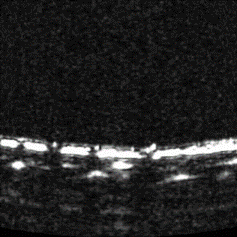

Cross sectional view

Surface(Depth) view

MAP